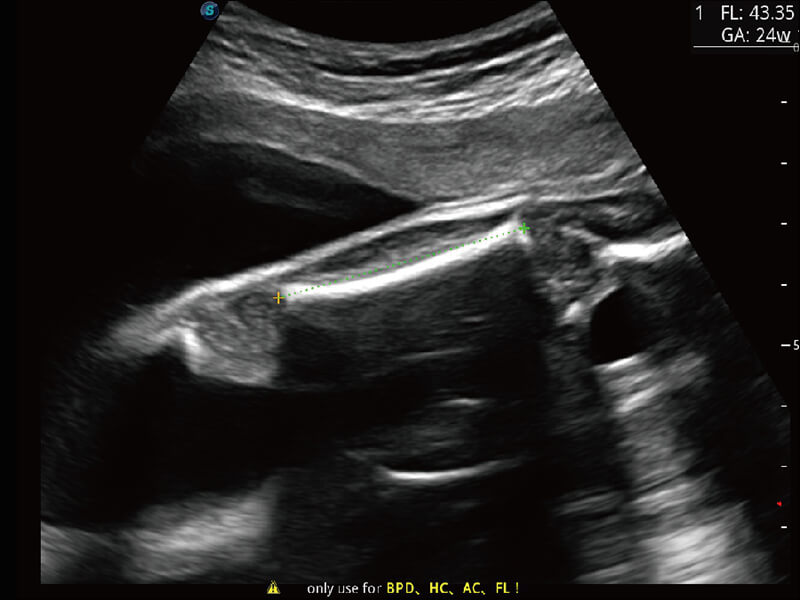

成像功能

S60探头工艺,从前端信号处理每一个环节采集无损声学数据,真实还原组织原貌,再现解剖细节。

超宽频带技术,为容积成像带来优质的二维图像基础,为您呈现丰富的结构细节,栩栩如生地展示宝宝的宫内形态以及各种组织的立体结构。